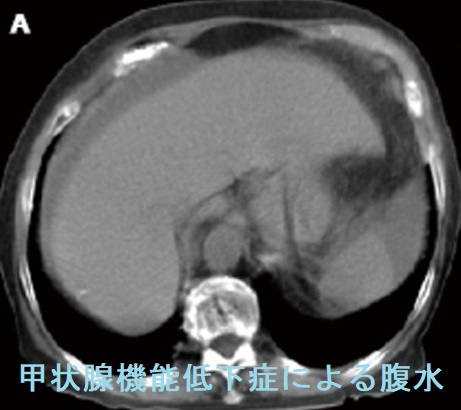

甲状腺機能低下症の4%未満に腹水(蛋白濃度が高い粘液水腫性腹水)。粘液水腫性腹水自体が腹膜を刺激し、卵巣癌の腫瘍マーカーCA125 の産生を増加させる。甲状腺ホルモン(チラーヂンS)補充療法により腹水は消失し、約1カ月遅れてCA125も正常値に。特に甲状腺ホルモン値(FT4,FT3)が低いと粘液水腫性腹水(腹水穿刺・利尿剤に反応悪く改善に時間を要す)・胸水(利尿剤で速やかに消失)・心嚢液(肺水腫、呼吸困難、右心不全、陰嚢・両下腿浮腫)貯留、腸管浮腫[甲状腺ホルモン剤(チラーヂンS)吸収障害]が出現。甲状腺乳頭癌、甲状腺未分化癌の腹膜播種がある。

甲状腺ホルモン(チラーヂンS)補充療法により腹水は消失して、CA125も正常値になります(甲状腺ホルモン正常化後、約1カ月遅れて)。

甲状腺機能低下症で、特に血中の甲状腺ホルモン値(FT4,FT3)が低いと、粘液水腫による腹水・胸水・心嚢液が貯留し易くなります。

甲状腺機能低下症による粘液水腫性腹水は、改善に時間を要しますが、治療目的で穿刺排液することは少ない。腹腔穿刺は腹水の性状確認、蛋白濃度測定、細胞診などの診断が目的です。腹腔穿刺はMcBurney 点や逆McBurney 点を穿刺するのが最も安全で、エコーガイド下の穿刺が望ましい。急速に大量の腹水を除去すると、ショックをおこす危険あり。